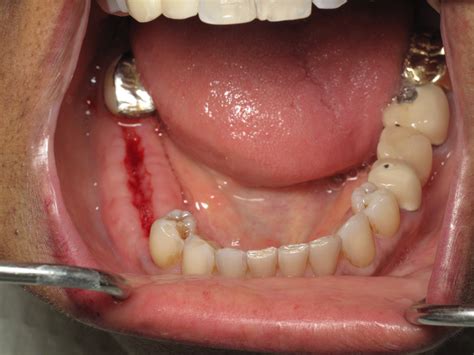

The process of placing a bone graft after tooth extraction is typically performed during the same appointment as the extraction itself. Once the tooth is removed, the dentist cleans the socket thoroughly to ensure no infection remains. The grafting material is then carefully packed into the space. A membrane is often placed over the site to hold the graft in place and protect the area from soft tissue ingrowth, ensuring the bone has the best chance to mature.

Recovery after a bone graft after tooth extraction is generally straightforward, but it requires patience to ensure the graft integrates properly. You will be provided with specific instructions regarding pain management and hygiene. It is normal to experience mild swelling or discomfort for the first few days. Avoiding strenuous activity and refraining from smoking is critical, as smoking significantly interferes with the bone regeneration process.